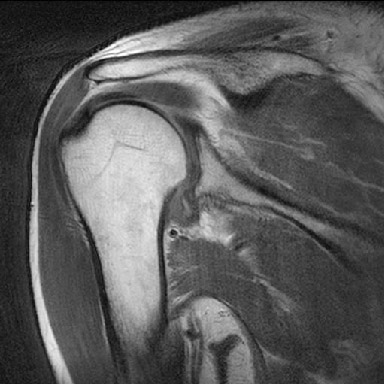

Rt.. Shoulder adhesive capsulitis

43세의 남성 환자 000씨는 5개월 전부터 우측 어깨가 아프고 팔을 움직이는 것이 힘들어 물리치료실을 찾았다. 5개월 전 버스를 타고 가던 중 버스가 급정거를 하면서 머리위의 손잡이를 강하게 잡으면서 어깨를 삐끗했다. 초기에는 통증이 목과 어깨 위쪽에만 있었으며, 방사되거나 퍼지지는 않았다. 주로 팔을 머리위로 올리는 동작에서 불편함을 느꼈다. 우측으로 누워서 잘 때면 통증이 심하여 잠을 깨곤 했고, 2개월 전 테니스도 그만 두었다. 통증 때문에 진통제를 먹곤 했다. 5일전 정형외과를 찾아 X-ray를 찍었으나 음성이었고, lidocaine 주사를 맞고 난 후 어깨 통증의 70% 정도가 경감되었다. 의사로부터 유착성 관절낭염의 진단과 회전근개 파열의 가능성에 대한 이야기를 들었다. 치료실에서 평가시 주사 치료 이전 통증의 50%정도가 남아 있었으며, 팔은 동작은 좀 좋아진 상태이다.

견관절낭염 환자의 방사선 영상